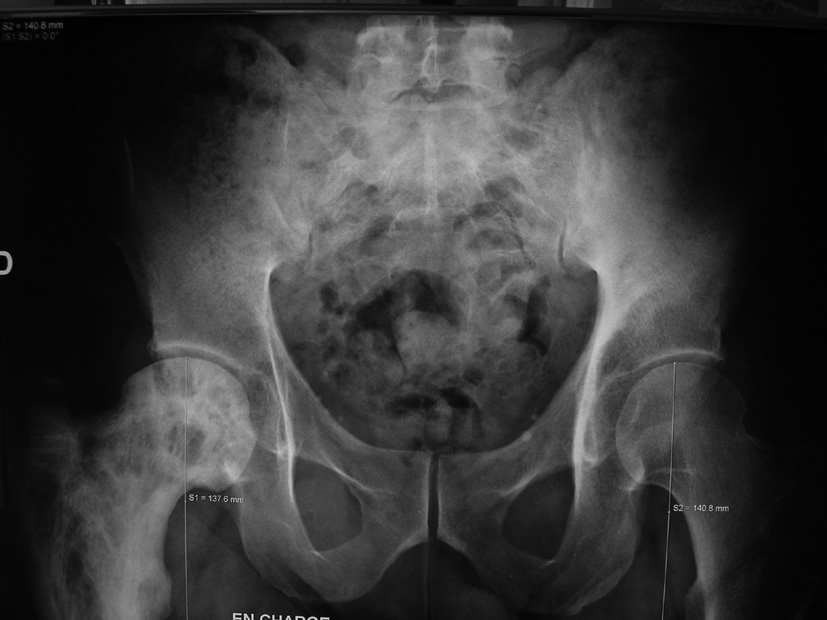

Monsieur M., quarante et un ans, arrive le dimanche soir dans le service des urgences où vous êtes de garde, pour une polyarthrite. Dans ses antécédents, vous notez une douleur de la racine de la cuisse droite depuis deux ans qui a déjà fait l’objet d’une exploration radiographique et scintigraphique (clichés ci-dessous). Dix-huit jours plus tôt est survenue une urétrite, contractée à Madagascar, traitée par ampicilline pendant sept jours.

Concernant la douleur de la racine de la cuisse droite depuis deux ans, comment l’expliquer vous ? Est-ce lié à la pathologie actuelle ?